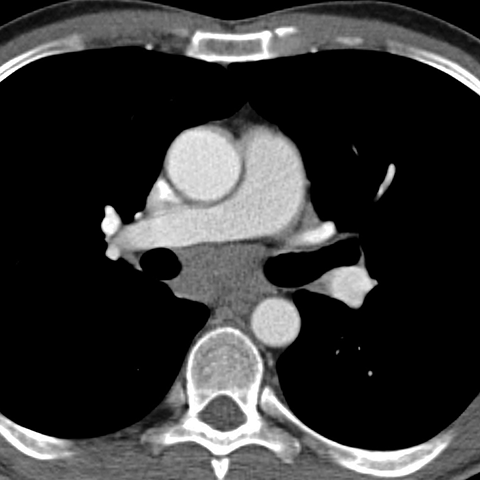

Mediastinal Lymph Nodes in NHL (Axial CT) [4 of 4]